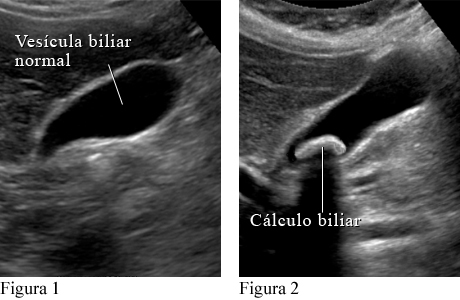

La prueba más común es una ecografía abdominal. Un auxiliar le pasa un transductor sobre el abdomen para generar imágenes en una pantalla. Pueden hacerse análisis de sangre para averiguar si los cálculos biliares están causando otros problemas graves o si los síntomas se deben a otra cosa.

Cómo se ve un cálculo biliar en una ecografía abdominal

Cortesía de Intermountain Medical Imaging, Boise, Idaho.

La figura 1 muestra una vesícula biliar normal en una ecografía. La figura 2 muestra un cálculo biliar grande en la vesícula biliar.